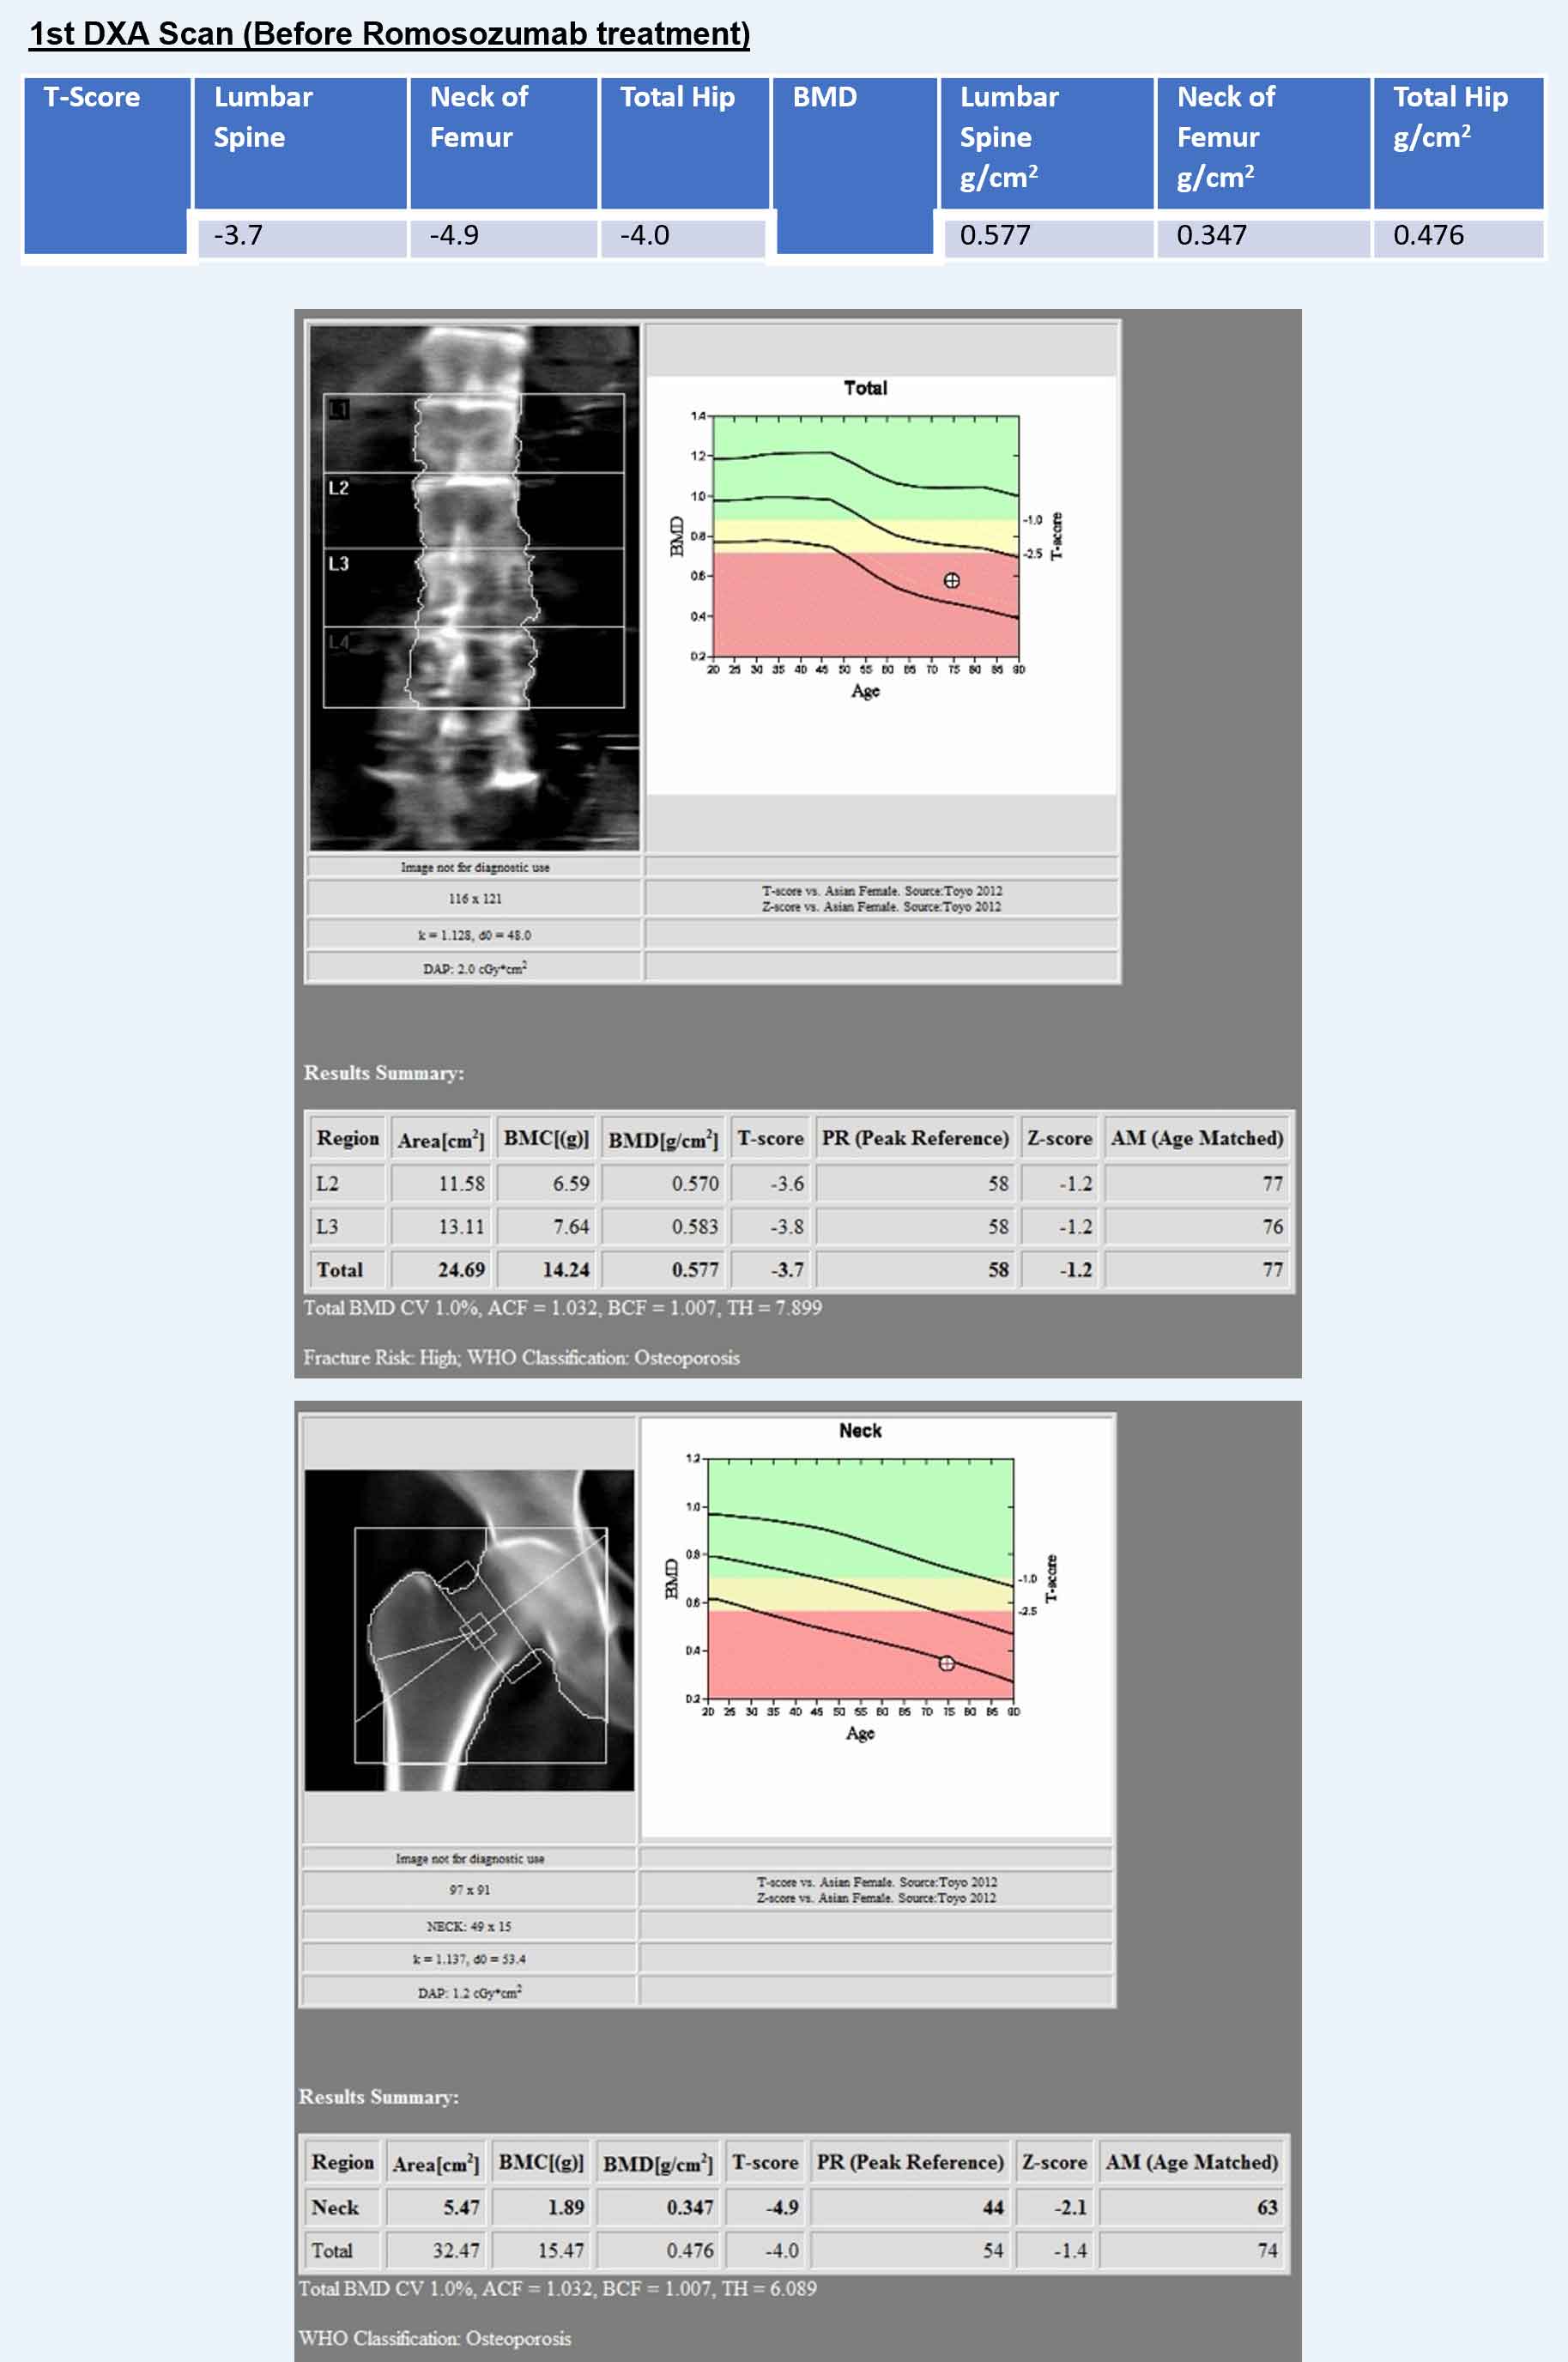

Hologic Horizon W

- LSC AP Spine 0.022 g/cm2

- LSC Neck of Femur 0.028 g/cm2

- LSC Total Hip 0.027 g/cm2

Changes in BMD after completing 1 year of Romosozumab

- Lumbar Spine = +0.149 g/cm2 (25.82%)

- Neck of Femur = +0.058 g/cm2 (16.72%)

- Total Hip = +0.078 g/cm2 (16.39%)

- Lumbar Spine: +0.149 g/cm2 (25.82%, LSC 0.022)

- Neck of Femur: +0.058 g/cm2 (16.72%, LSC 0.028)

- Total Hip: +0.078 g/cm2 (16.39%, LSC 0.027)

All the increases in these three parameters were higher than the respective LSC.

- The 1st DXA Scan of hip and spine was performed after the left hip surgery.